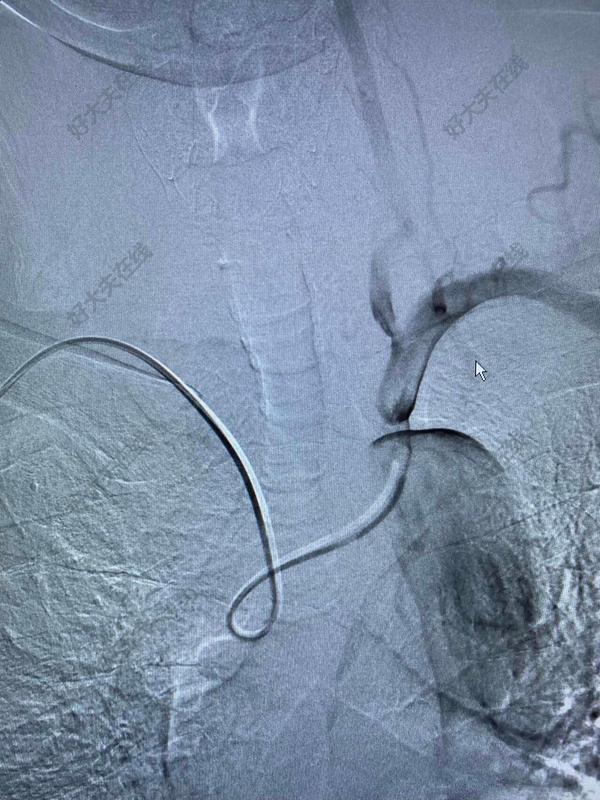

講話不清可以治療嗎?72歲老年男性,講話含糊不清伴反應(yīng)遲鈍9月余。老人家在口服抗血小板藥物、他汀藥物和控制高血壓、糖尿病的過程中,近9個(gè)月來一直講話含糊不清,并呈越來越重的趨勢,反應(yīng)能力也不是很好,由于以前發(fā)生過腦梗塞,家人也就認(rèn)為可能是以前的腦梗塞留下的后遺癥,只能慢慢康復(fù)了……最近,兒子帶老人家過來復(fù)查,檢查發(fā)現(xiàn)右側(cè)椎動脈起始部的狹窄越來越重,和9個(gè)月前相比,簡直判若兩人(管),左側(cè)椎動脈又先天發(fā)育不好……,看來保守治療吃藥不太行,還得需要外科干預(yù)和家屬商量后,我們采用全球首款椎動脈專用藥物洗脫支架(Maurora)成功精準(zhǔn)切線位植入,消除了這個(gè)“卡脖子”的狹窄……術(shù)后隨訪結(jié)果:老人家說話口齒清晰了,思維反應(yīng)也快了……按照說明說的介紹,與裸支架相比,Maurora可以降低再狹窄率66/……